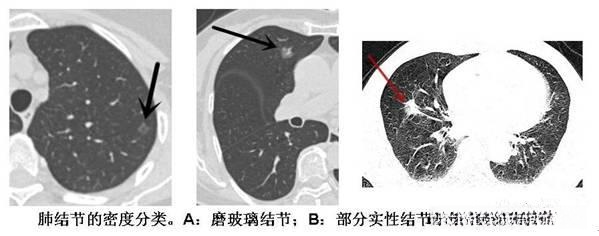

肺结节的分类 (根据密度分类:)

1、实性肺结节:

是一个在CT下呈现白色的高密度的影子,表面光滑小而圆。

2、纯磨玻璃结节:

CT扫描显示肺内密度略微增高;即使在病灶处也能观察到肺纹理特征,并如同经过磨玻璃般的审视一般。磨玻璃结节在临床中的检出率较高

3、混合磨玻璃结节:

具有实体成分的混合型磨耗性玻璃样结节具有较高的恶性发生倾向,并易演变为肺腺癌,在临床中多见于单纯性毛玻璃样结节的情况